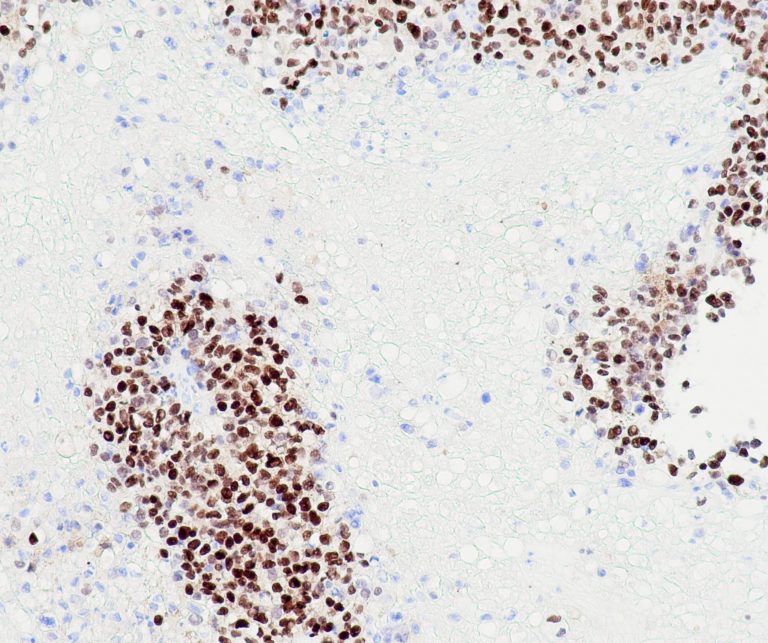

Vascular Pathology

Gastrointestinal (GI) Pathology

General Marker

Breast Pathology

Endocrine Pathology

Gynecological Pathology

Neuropathology

Infection Markers

Lung Pathology

Urinary Tract Pathology

Transplantation Pathology

Soft Tissue Pathology

Hematopathology